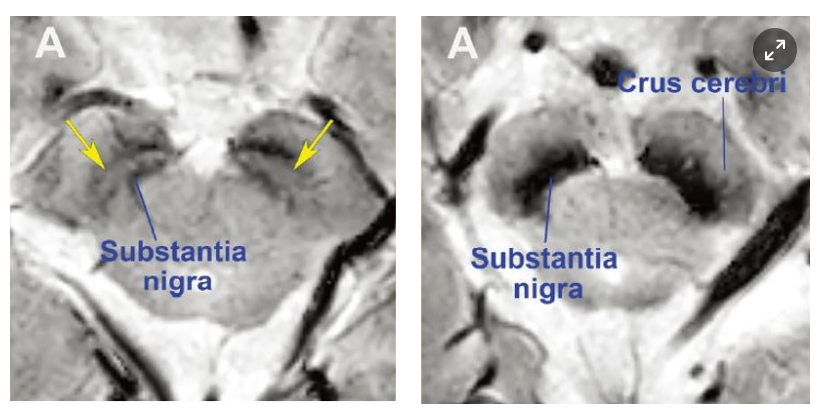

파킨슨병은 치매 다음으로 흔한 대표적인 퇴행성 뇌질환이다. 전형적인 파킨슨병은 발현 증상과 신경학적 검사만으로 진단이 가능하다. 하지만 파킨슨 증후군이나 이차성 파킨슨증처럼 증상이 유사한 다른 병과 구별하기 위해선 MRI처럼 영상의학적 검사가 필요하다.

- 흑질의 도파민 감소: 흑질에서 생성되는 도파민은 운동 조절에 중요한 역할을 하는데, 이러한 도파민이 감소하면 운동 기능에 문제가 발생합니다.

- 뇌 영상 검사: 뇌 MRI, PET-CT 등을 통해 뇌의 구조적 변화를 확인합니다.